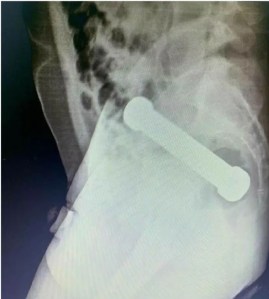

Após a realização de um exame de raio-X, os profissionais de saúde encontraram um peso de dois quilos, de cerca de 20 centímetros de comprimento (que são usados em academias de ginástica para exercícios de membros superiores) dentro do paciente. O halter estava localizado entre o reto e o intestino grosso do homem, que, depois do exame, admitiu ter introduzido o peso de academia no corpo para obter satisfação sexual.